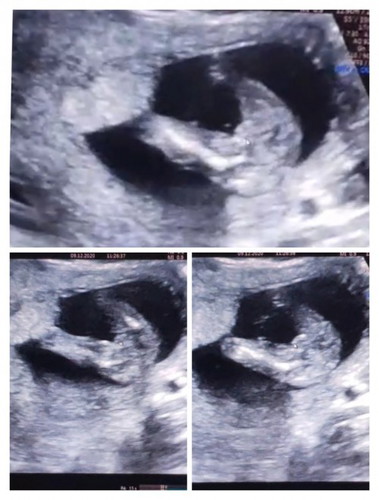

16w kurg jelas. cuba lg tgk masa 19-20w 🙂

gegirl ni. Nampak burger 😘

Looks like girl

Mcm girl ni

Bby girl

mcm girl